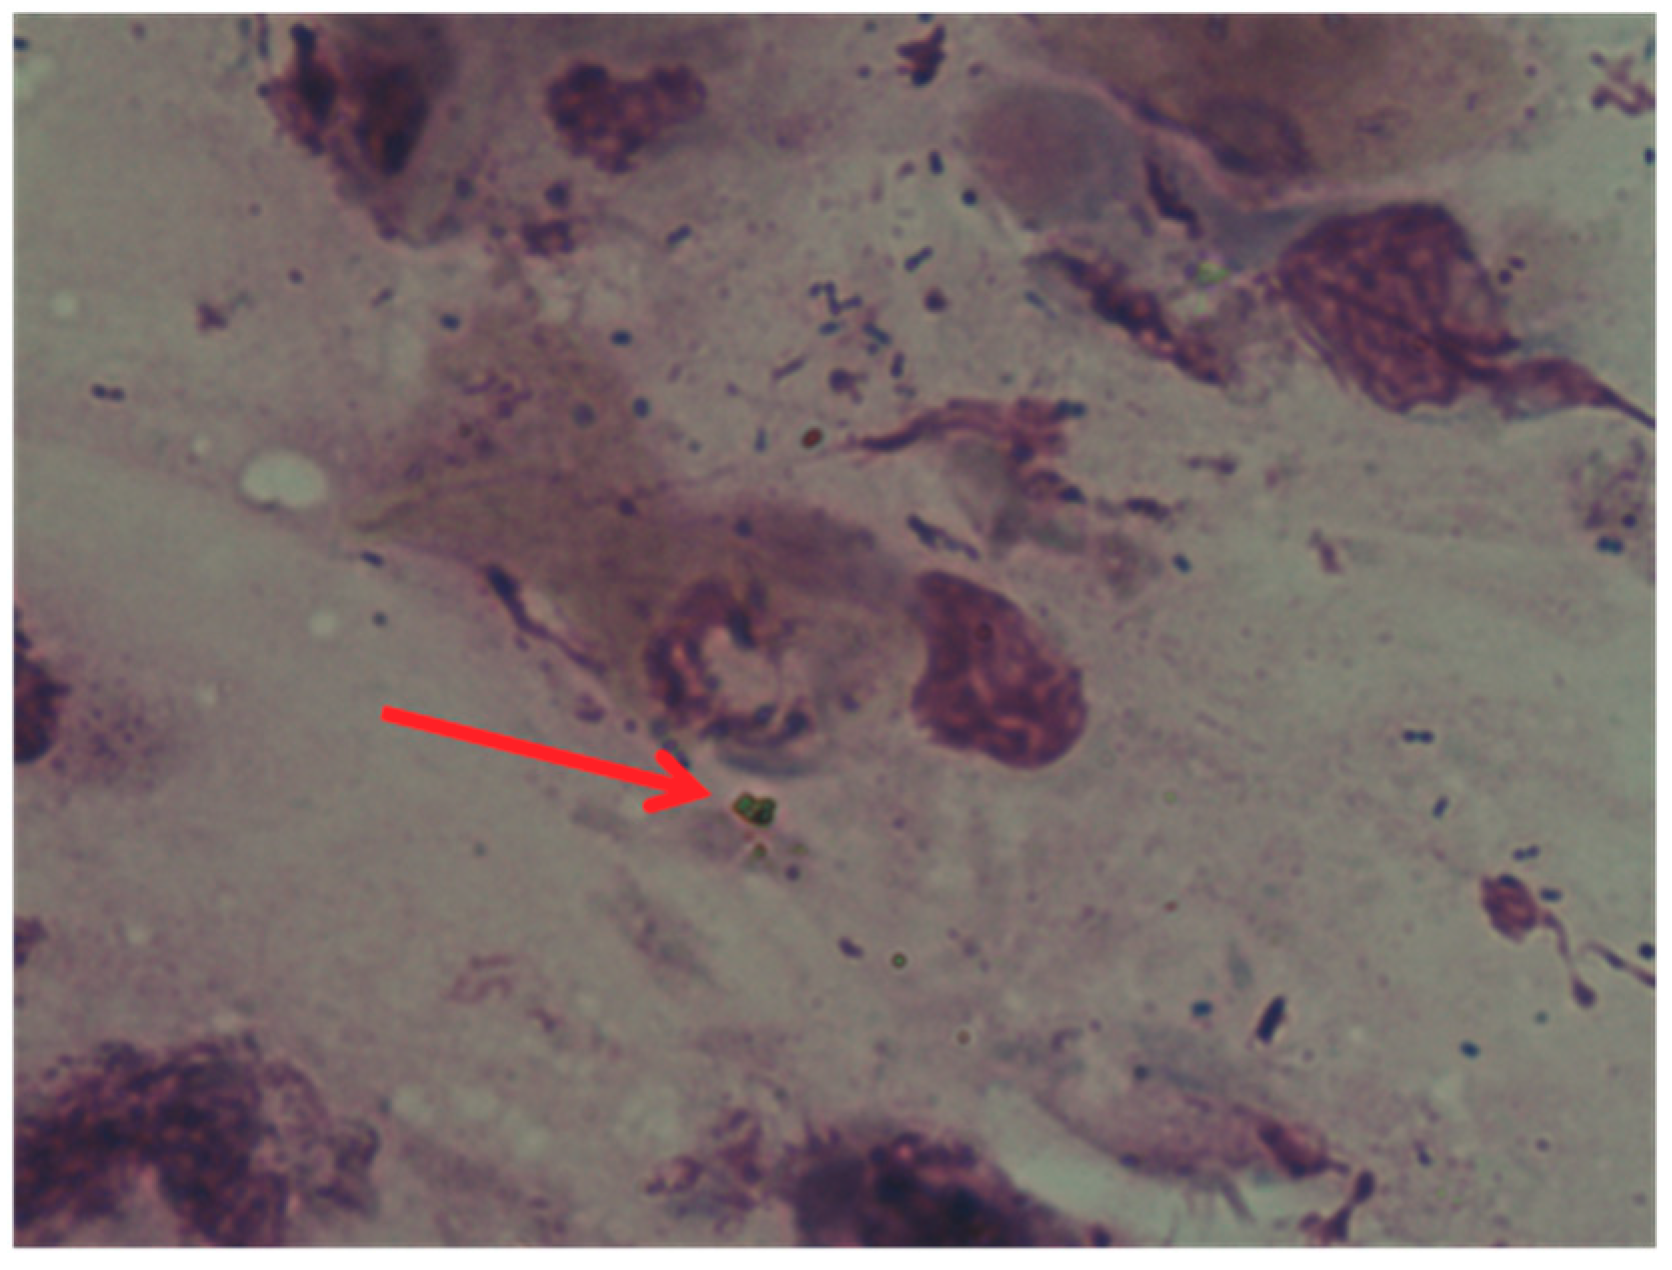

Identification and Characterization of Nasal Polyposis and Mycoplasma Superinfection by Scanning Electron Microscopy and Nasal Cytology with Optical Microscopy: A Case Report

2. Clinical Case